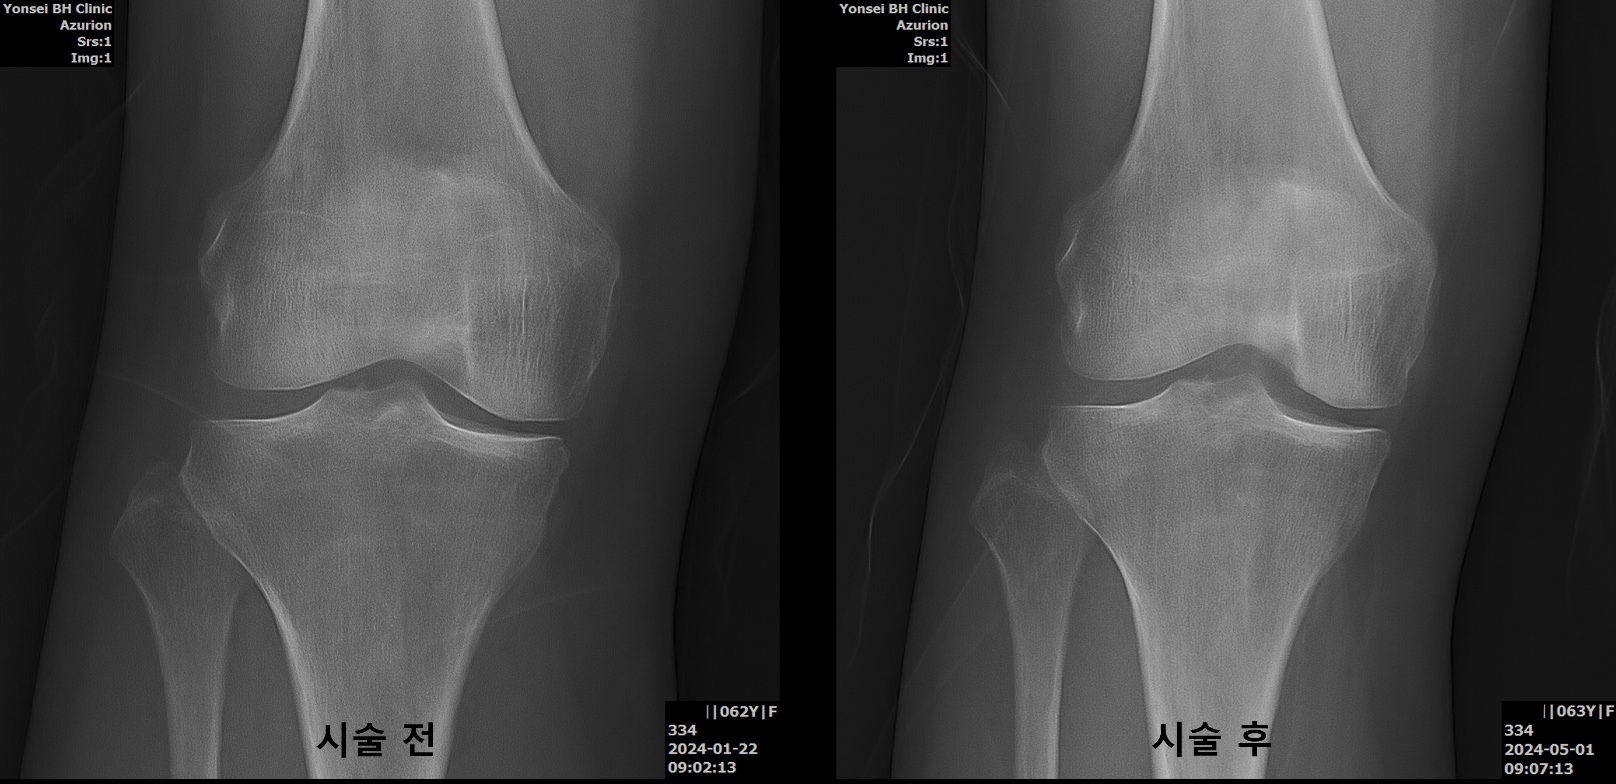

무릎 관절염 치료 시술 전후